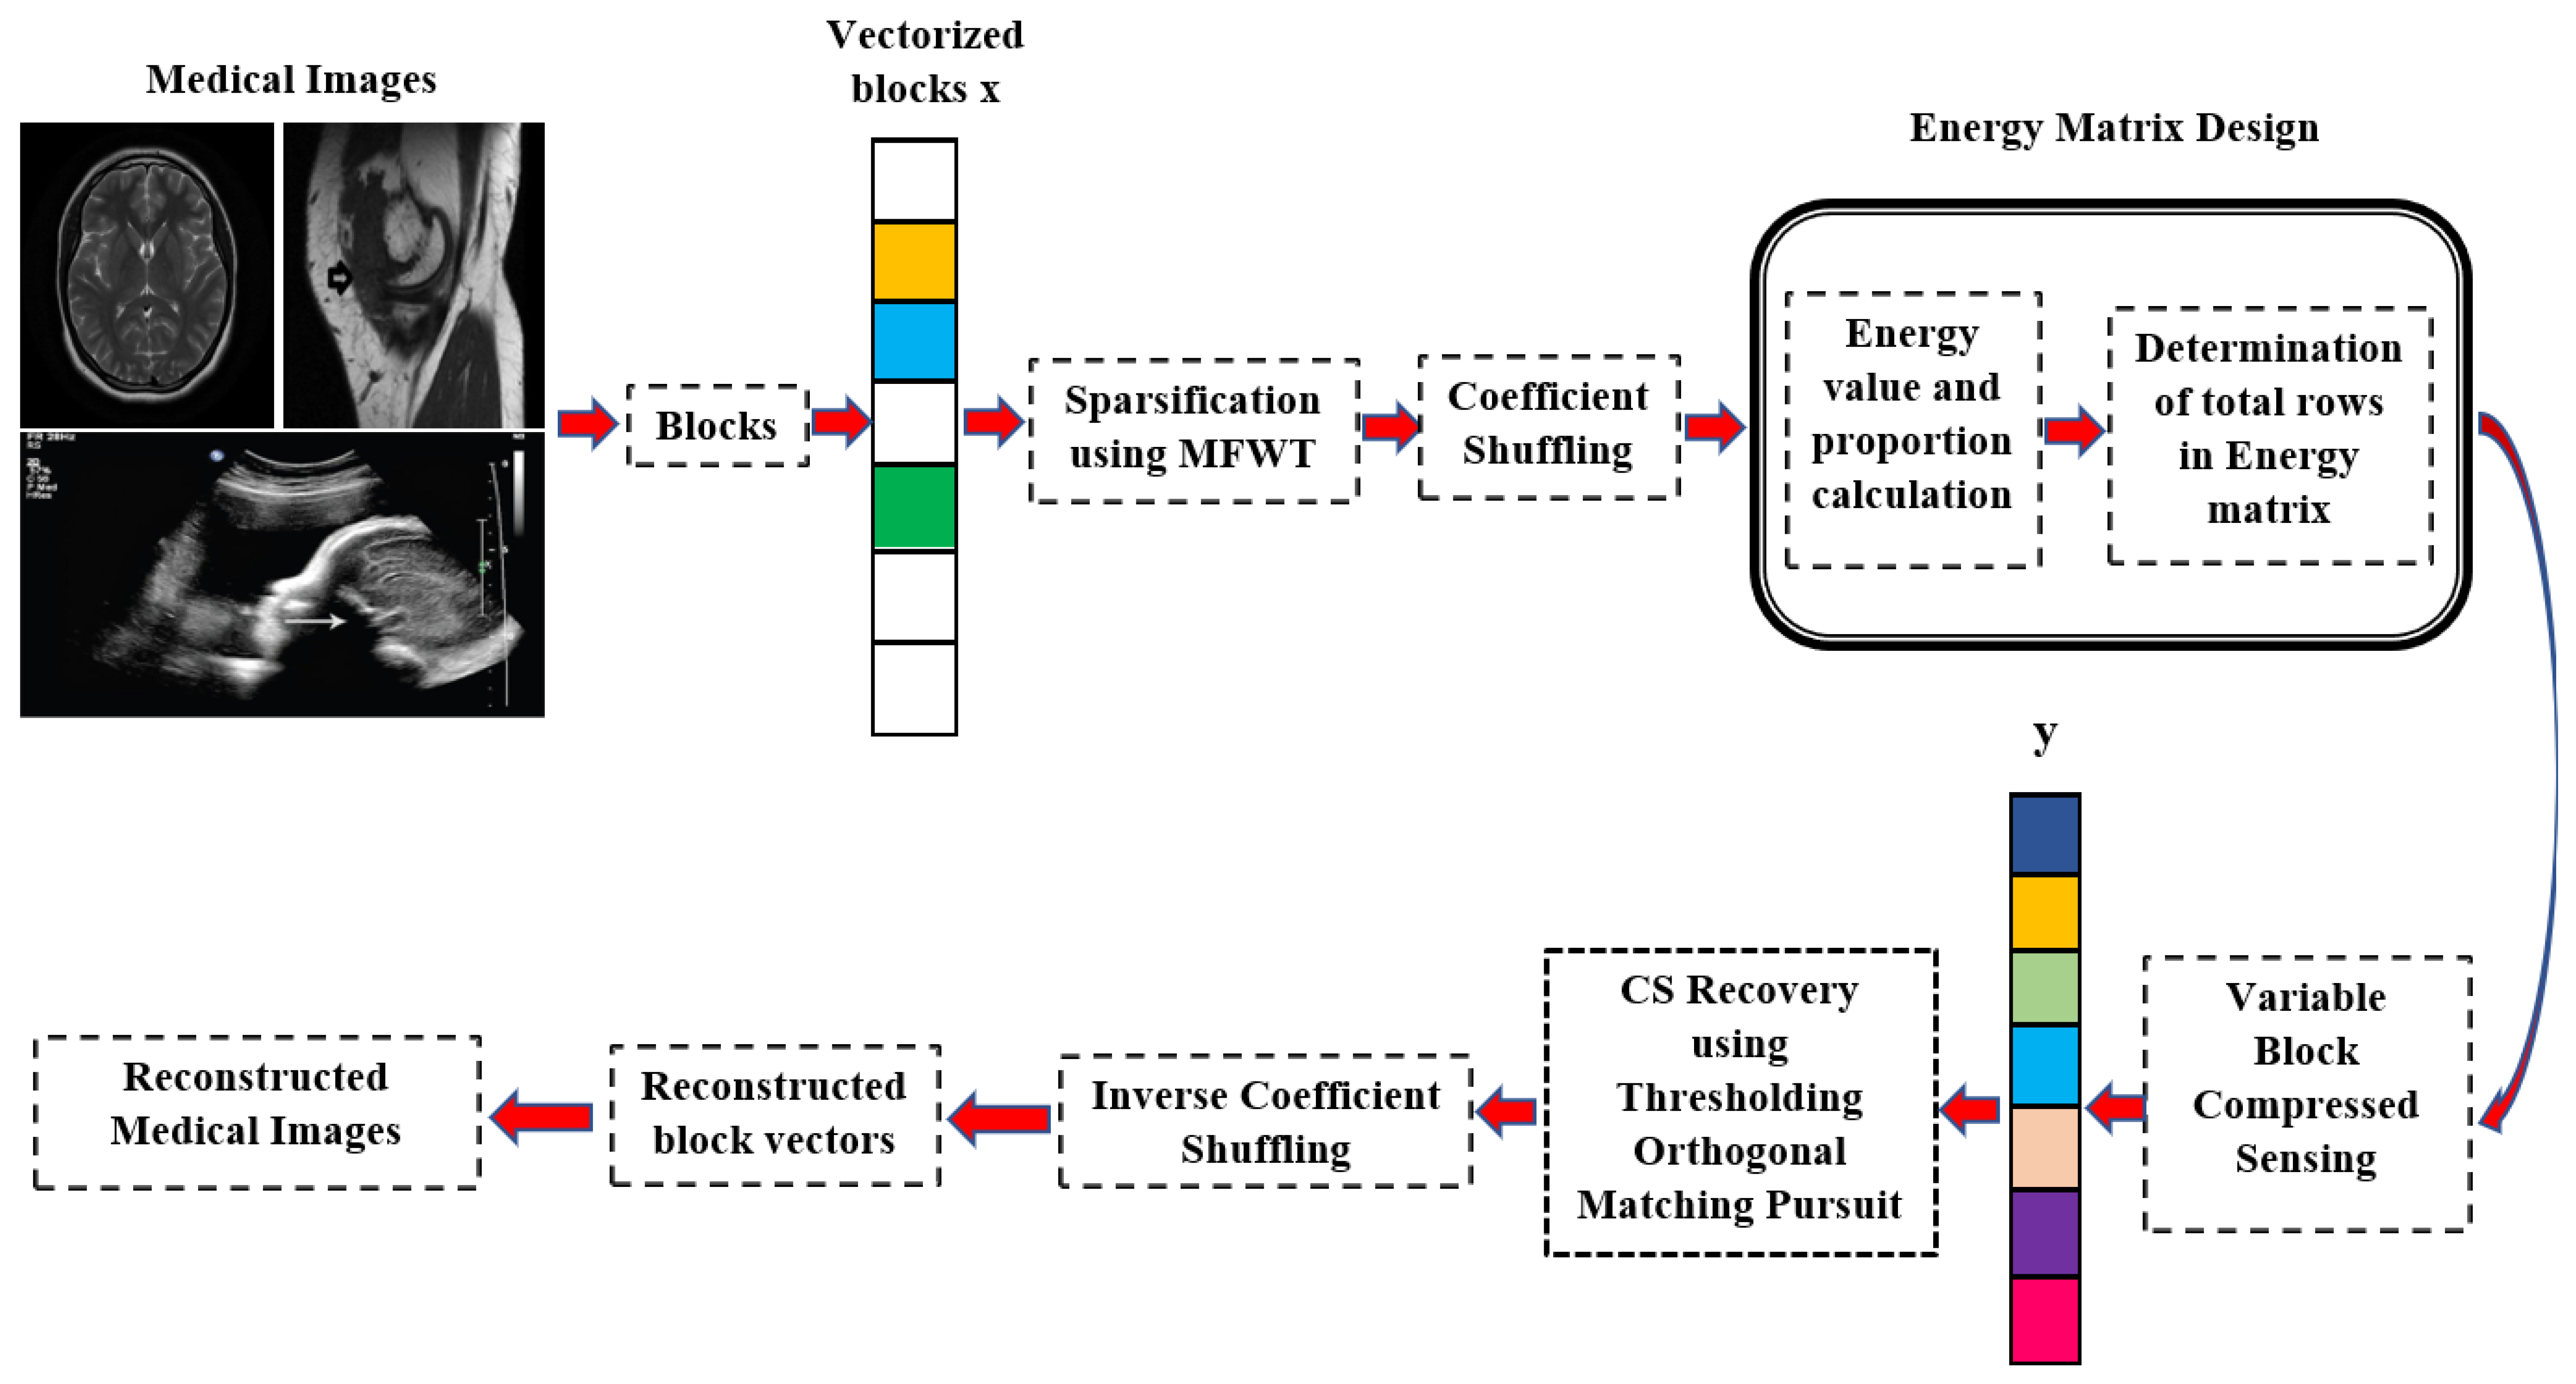

3. Proposed Coefficient-Shuffled Energy Matrix-Based VBCS (CSEM-VBCS)

3.1. Energy Matrix Design

3.2. Coefficient-Shuffled Variable Block Compressed Sensing